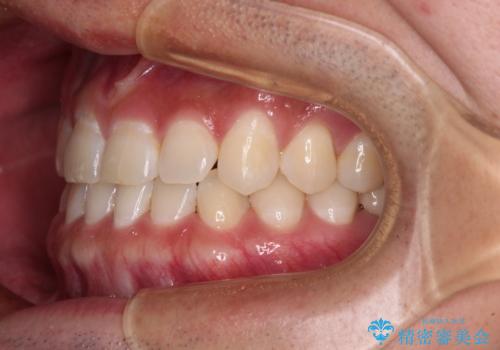

下顎前歯の叢生解消も提案しましたが、上顎の隙間が閉じたことで満足されました。

空隙歯列弓はマウスピースによる保定を行っても、すぐに後戻りを起こしてしまうため、ワイヤーリテーナーによる保定を併用することとしました。